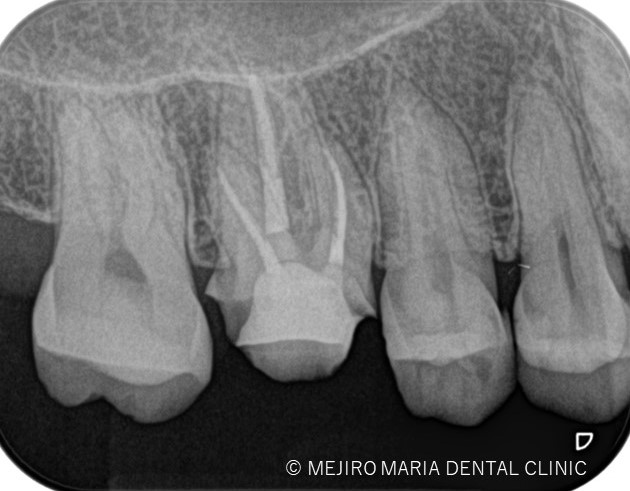

3日前よりズキズキする痛みを感じ始め、初診当日は頭に突き抜ける痛みがあることを主訴に来院された患者様です。

症状は冷たい物、温かいものを食べたときの痛みを訴えておられました。

術前の診査より持続性(長い時間)の冷温痛、打診痛を確認し、当院では不可逆性歯髄炎と診断しました。

歯科用拡大鏡、歯科用顕微鏡下にて、軟化象牙質(虫歯)を除去後、歯髄を確認すると一部の歯髄には血流がなく部分壊死を起こしていることがわかる。

う蝕などの感染による歯髄炎から歯髄壊死への移行期に激痛が生じる場合が多い。

今回は術前に歯髄炎による疼痛を確認していたため、水酸化カルシウムを貼薬した後、2回目の治療にて根管充填、支台築造処置を終了させている。